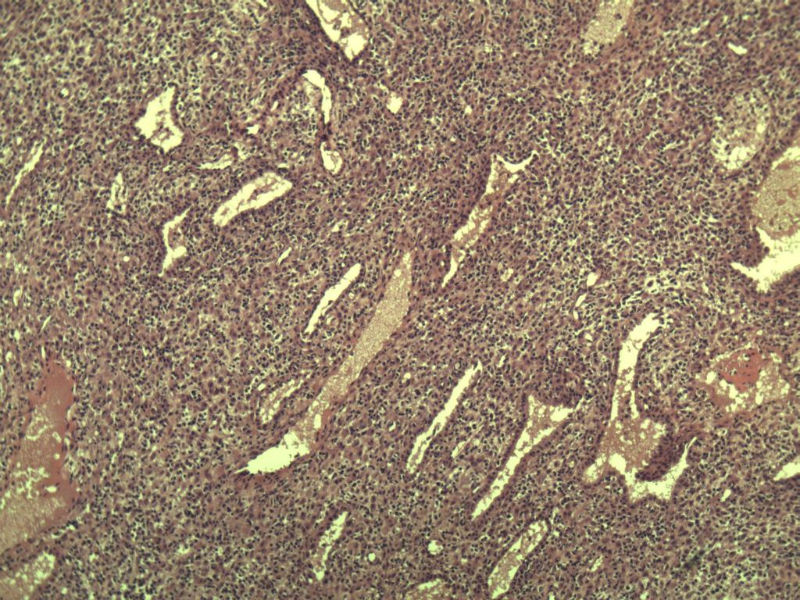

这是另外一个 40岁 经期延长 流血量增多 半年 这是蜕膜样变吧 有什么意义吗? 要报告不?